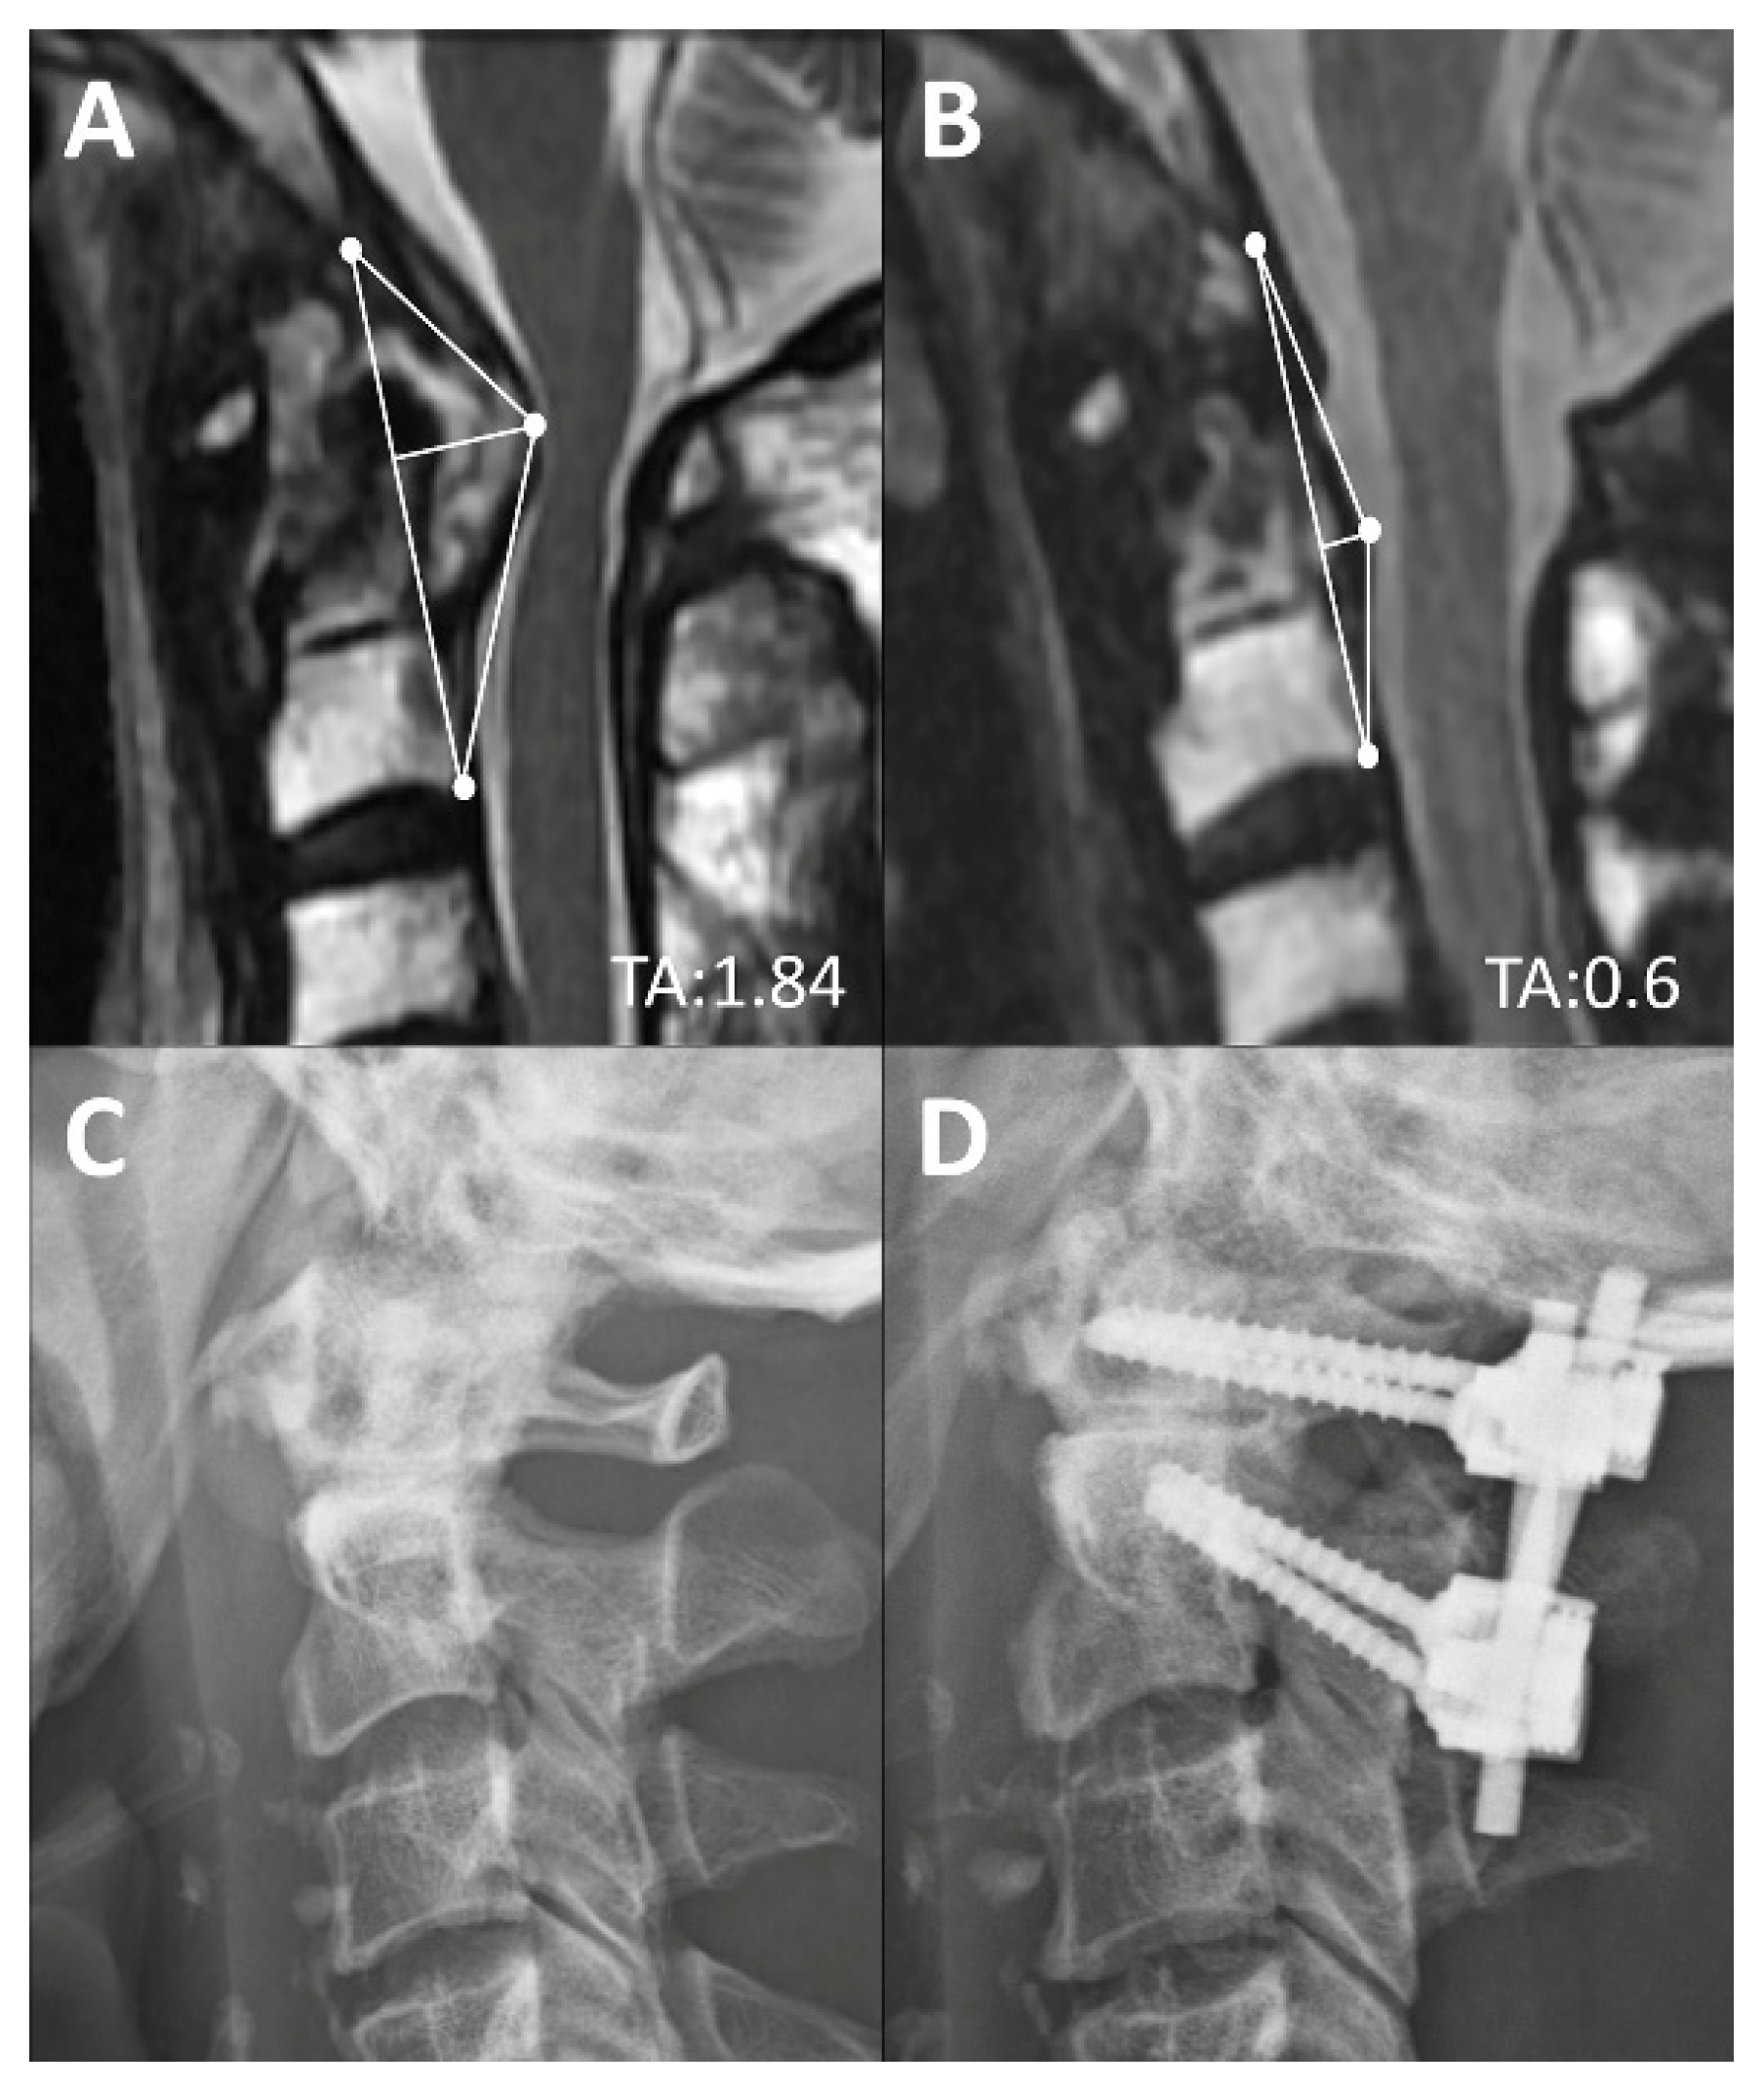

| Surgery (n = 81) | 1.67 ± 0.51 | 1.34 ± 0.47 † | 1.21 ± 0.37 † |

| Complete Reduction (n = 47) | 1.52 ± 0.44 | 1.12 ± 0.39 † | 1.03 ± 0.39 † |

| Partial Reduction (n = 34) | 1.81 ± 0.52 | 1.59 ± 0.46 † | 1.41 ± 0.2 † |